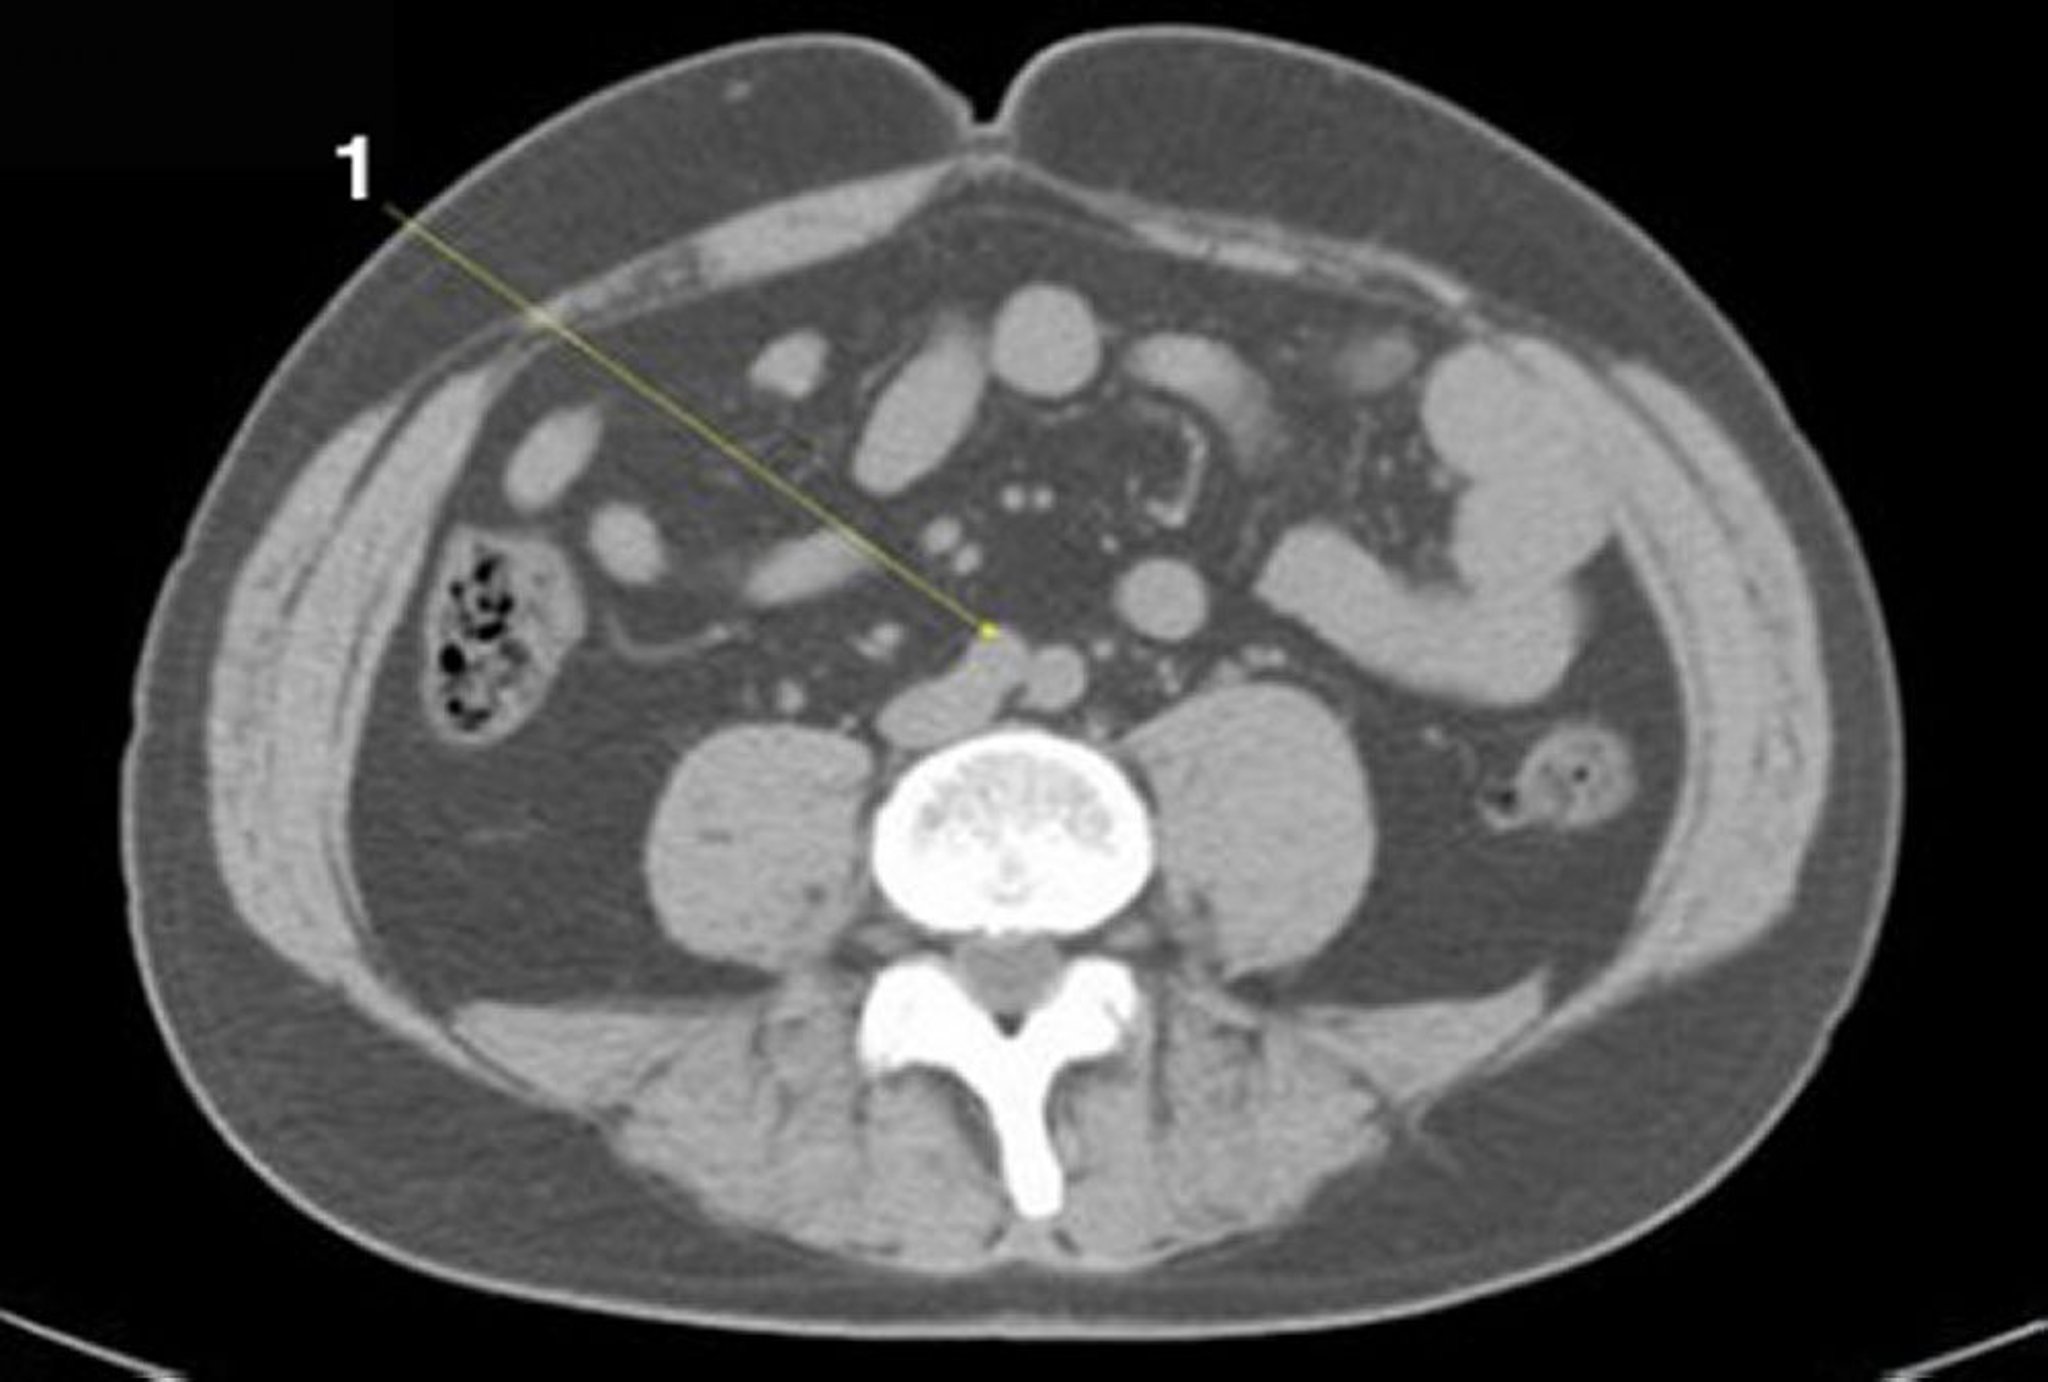

Noncontrast CT Scan of the Abdomen and Pelvis Showing Normal Anatomy (Slide 20)

1 = aortic bifurcation.